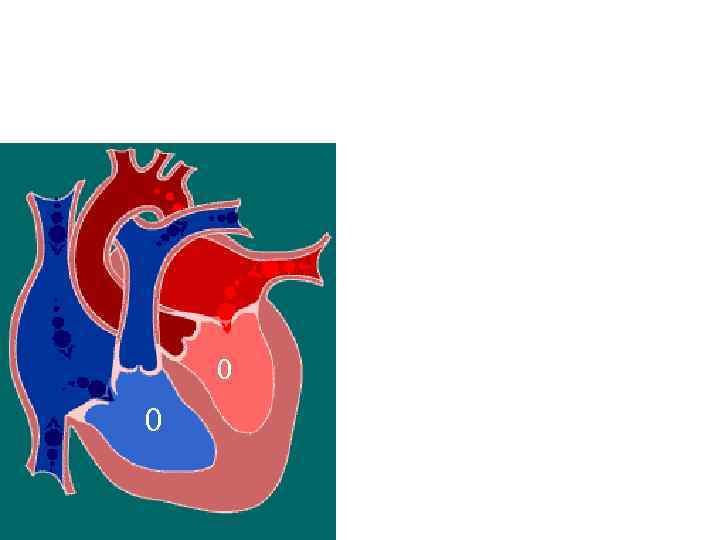

Диастола желудочков Фаза расслабления Клапаны: створчатые - закрыты полулунные – закрыты Давление в желудочках: -правом – 0 мм рт. ст 0 0 - левом – 0 мм рт. ст Гемодинамика: отсутствует

Диастола желудочков Фаза расслабления Клапаны: створчатые - закрыты полулунные – закрыты Давление в желудочках: -правом – 0 мм рт. ст 0 0 - левом – 0 мм рт. ст Гемодинамика: отсутствует